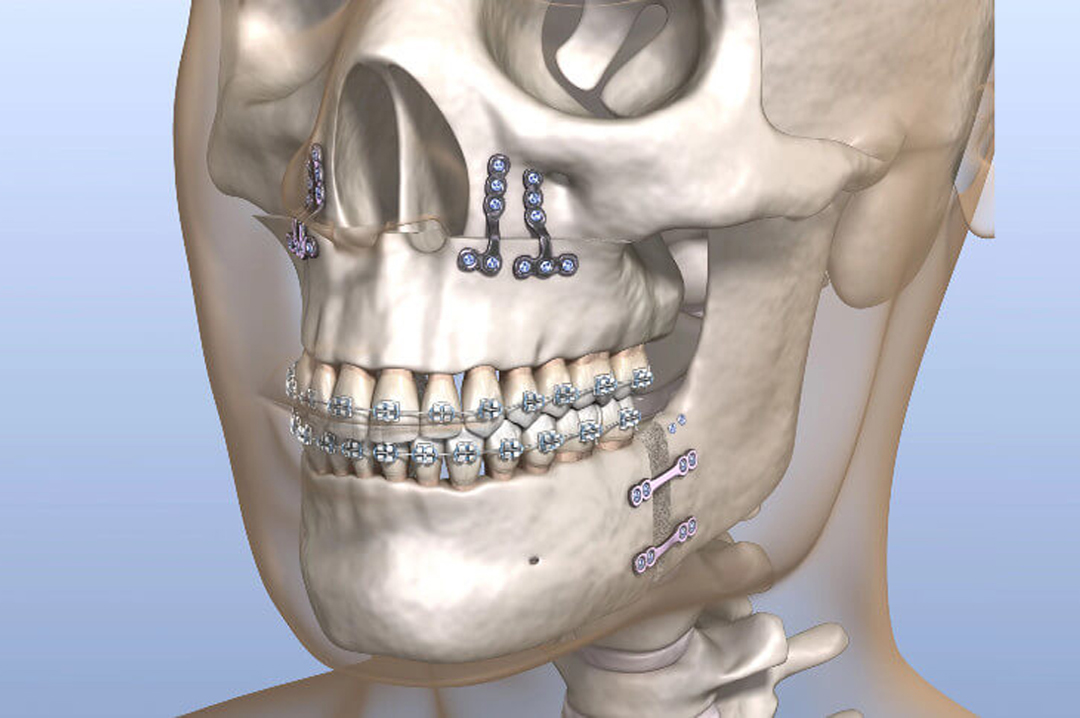

Ortodoncia Quirúrgica

Corrección integral de la mordida mediante ortodoncia y cirugía.

La ortodoncia quirúrgica está indicada en casos donde la maloclusión se debe a una desalineación ósea.

Combina brackets o alineadores con cirugía ortognática para lograr una mordida funcional, mejorar la estética facial y obtener resultados estables a largo plazo.